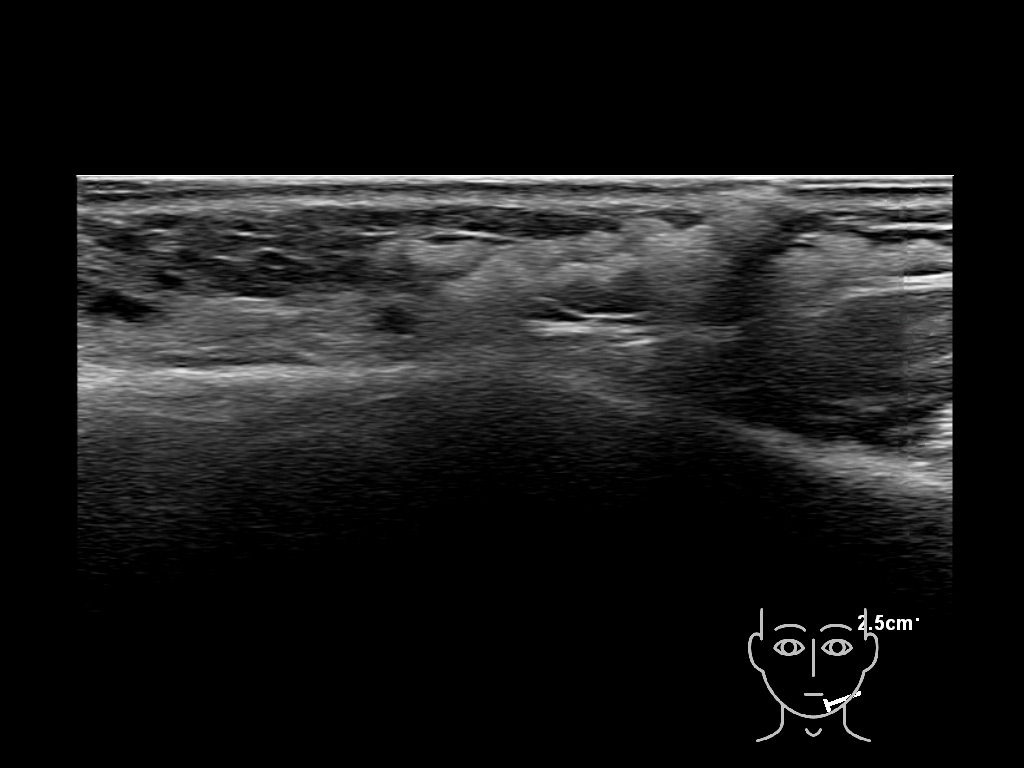

Draw in the image on the right where the fillers are located. To check if your answer is correct, please click on the secondary image.

Draw in the second image below where the fillers are located. To check if your answer is correct, swipe the first image to the right.